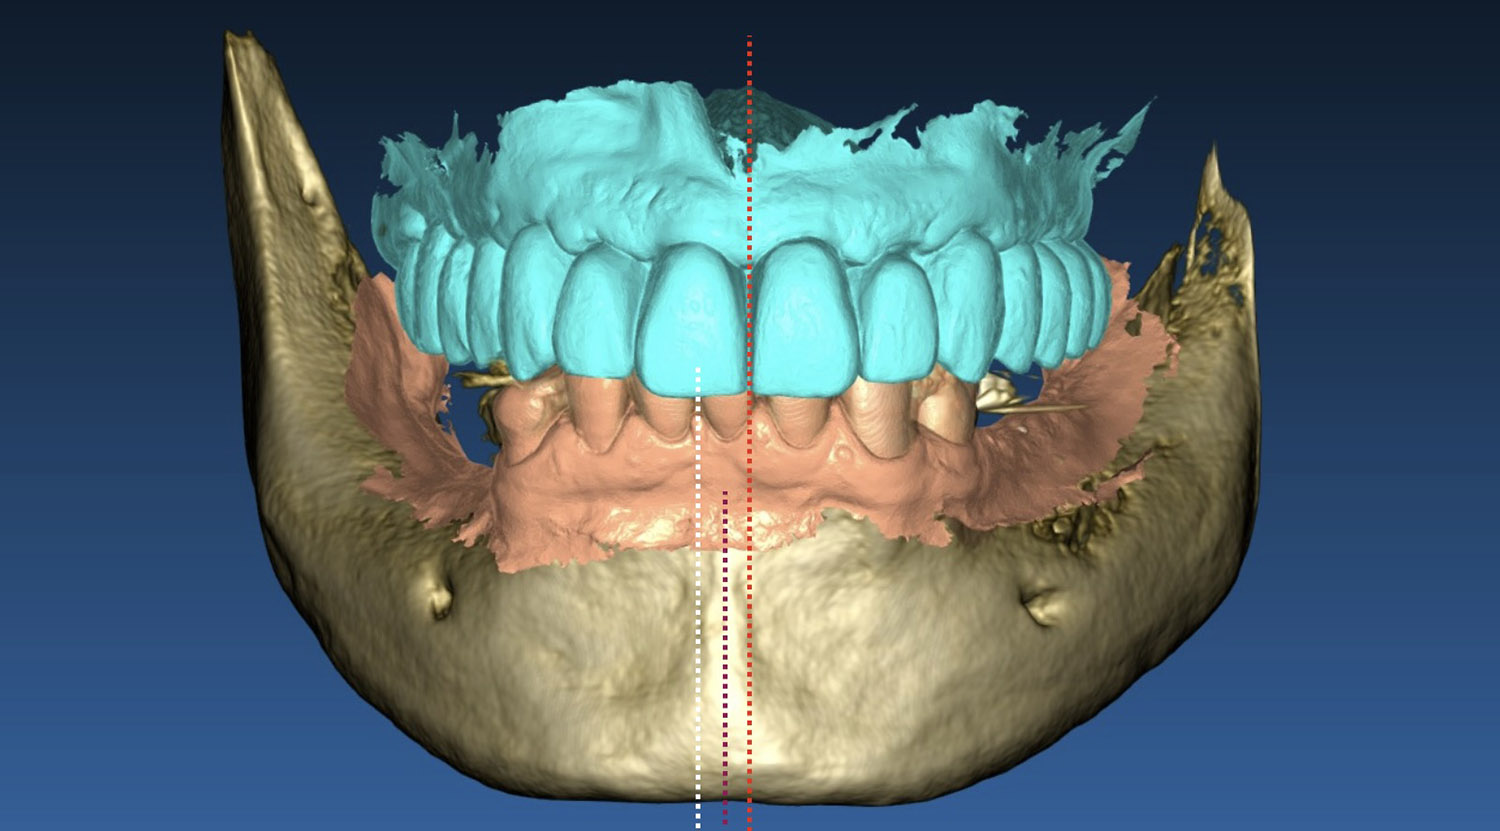

È una tecnica basata su un rivoluzionario sistema di pianificazione del trattamento attraverso la chirurgia guidata, che al giorno d’oggi rappresenta la massima evoluzione nell’implantologia dentale. Questa disciplina infatti consente al medico di pianificare l’intervento chirurgico al computer sulla base di un’indagine Tomografia Assiale Computerizzata.

Il sistema permette al clinico di progettare al computer la posizione e la dimensione esatta degli impianti prima dell’intervento chirurgico utilizzando la ricostruzione tridimensionale (3D) di una zona o dell’intera arcata dentale per poi richiedere ad un centro specializzato la costruzione di una guida chirurgica estremamente precisa che permetterà di eseguire un intervento atraumatico.